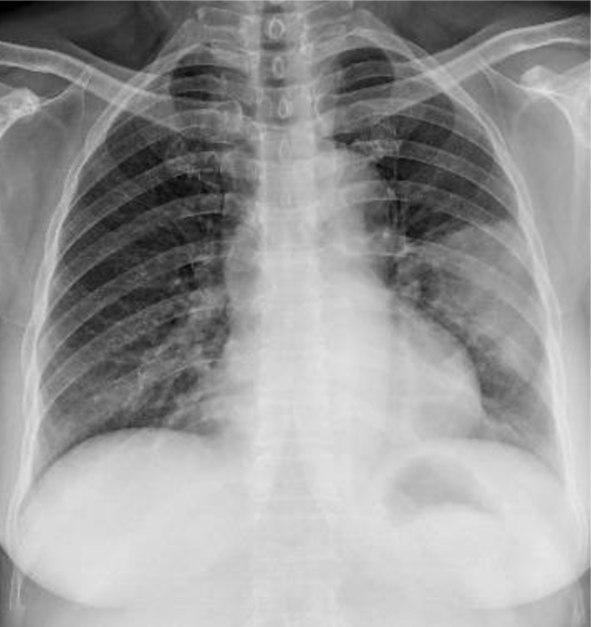

1-Mờ đồng nhất phổi (T) phân thùy lưỡi kèm hình ảnh nội khí quản bên trong => Viêm phổi + đông đặc phổi 2-Cung động mạch chủ dãn